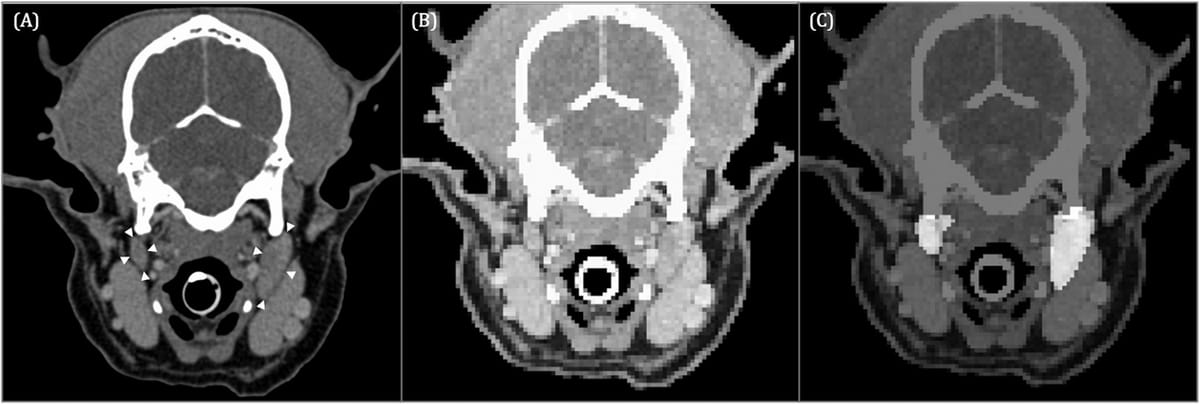

Transverse contrast-enhanced CT image of a 9-year-old Shetland Sheepdog acquired in sternal recumbency (window width = 450, level = 140, 120 kVp, 280 mA) (A) at the level of the paracondylar processes showing the medial retropharyngeal lymph nodes (white arrowheads). Input image for U-Net (B) and corresponding output image (C). The pixels identified by U-Net as medial retropharyngeal lymph nodes are highlighted in image (C). Left in the images is right in the dog